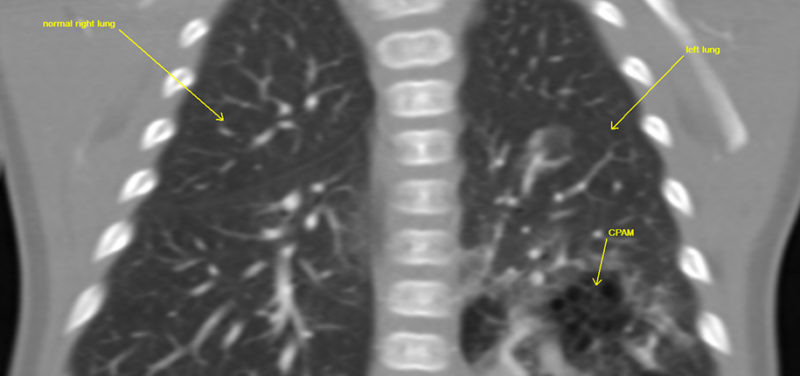

For example, one of our cardiothoracic radiologists, a doctor who looks at images of the heart, lungs and airway, is working with one of our fellows to see if there is a better way to look at infants with a lung abnormality known as CPAM (congenital pulmonary airway malformation). A CPAM is an abnormality of lung development that can make it difficult for a baby to breathe when he or she is born. A CPAM can also rarely lead to cancer if it is not removed. As a result, surgery is usually necessary to remove the CPAM.

Before surgery, a CT scan is often requested to see the size and location of the CPAM and to see if there are any abnormal blood vessels flowing into or out of the CPAM. This CT scan provides important information to the surgeon, which allows for faster operations with fewer complications.

Traditionally, the CT scan done to look at the CPAM is designed to focus on the blood vessels using a technique called CTA (CT angiography). Our research team found that using a standard CT technique was able to answer the surgeon’s questions just as well as the CTA technique and at HALF the radiation dose! See if you notice any difference between the image obtained with the traditional CTA technique and the image obtained with the standard CT technique, as shown below.

Image: CT coronal image right lower lobe CPAM with abnormal blood vessel.

Image: CT coronal image right lower lobe CPAM with abnormal blood vessel.

Image: CTA coronal image left lower lobe CPAM with abnormal vessel.

Image: CTA coronal image left lower lobe CPAM with abnormal vessel.